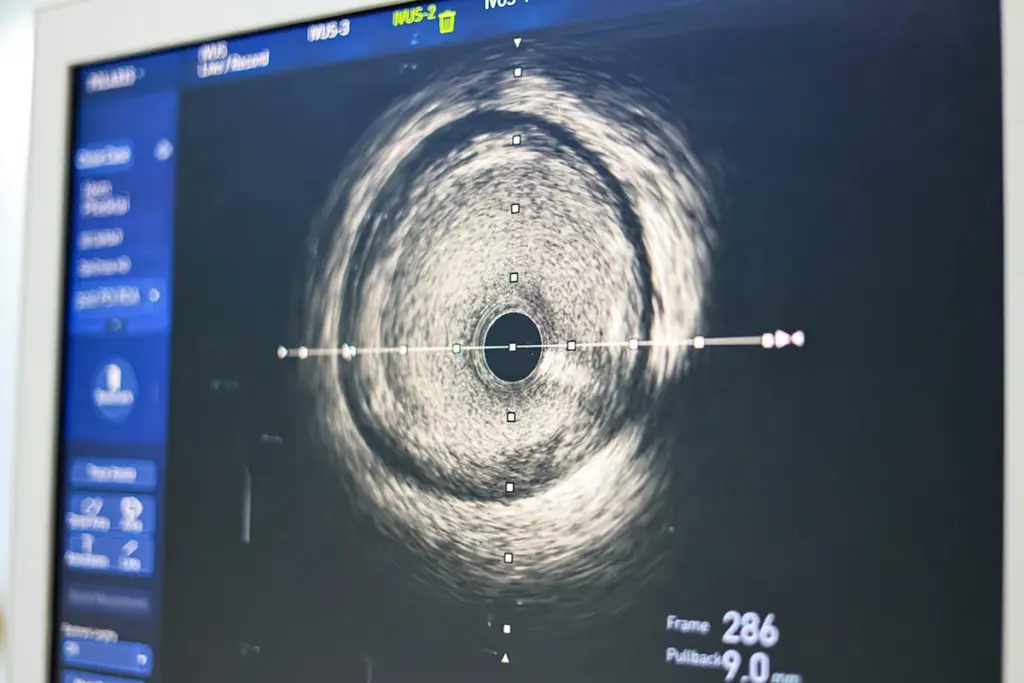

Differences with Intravascular Ultrasound

Intravascular ultrasound (IVUS) gives detailed views of the arteries. It helps see plaque and stent placement. But, it doesn’t tell us how well the artery works.

Key differences between FFR and IVUS include:

- FFR measures pressure gradients across a lesion, indicating its functional significance.

- IVUS provides high-resolution images of the coronary artery lumen and wall.

In conclusion, while angiography and IVUS give us important details, FFR directly checks how well a stenosis works. This shows why FFR is important in making better treatment choices.